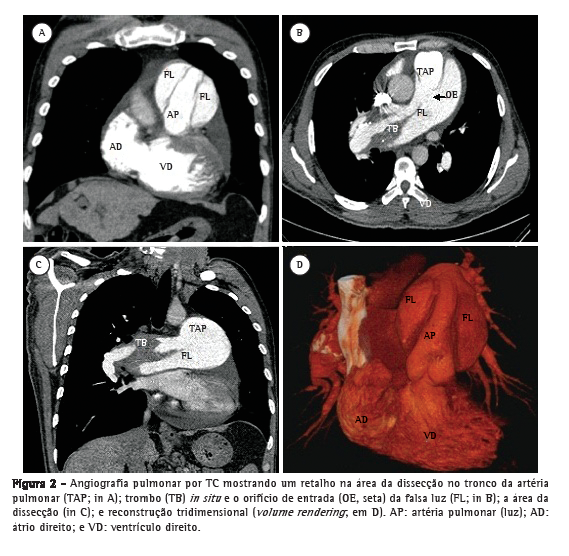

Paciente do sexo masculino, 50 anos, diagnosticado há quatro anos com hipertensão pulmonar relacionada à esquistossomose mansoni, admitido na emergência do Hospital das Clínicas da Faculdade de Medicina da Universidade Federal de Minas Gerais, localizado em Belo Horizonte, Brasil. Apresentava dor torácica retroesternal de início recente com agravamento progressivo e falta de ar (hipertensão pulmonar classe funcional III, de acordo com a Organização Mundial de Saúde). Havia sido diagnosticado com leucemia mieloide crônica há sete meses e estava em quimioterapia desde então. No momento da internação, o ecocardiograma transtorácico mostrava um grande trombo central não obstrutivo na artéria pulmonar principal direita. O átrio direito estava dilatado, e havia regurgitação tricúspide leve, com pressão sistólica em artéria pulmonar estimada em 63 mmHg. Foi diagnosticado como portador de trombose in situ como complicação de hipertensão pulmonar de longa duração. Após a possibilidade de síndrome coronária aguda ter sido excluída, recebeu alta em uso de varfarina. Foi reinternado dois meses depois em razão de dor torácica refratária com agravamento progressivo. Na época, apresentava SpO2 de 96%, e uma terceira bulha era audível no espaço paraesternal esquerdo inferior, acompanhada por murmúrio de regurgitação tricúspide. Os pulmões estavam limpos, e os pulsos arteriais periféricos estavam simétricos. Os exames laboratoriais estavam normais, incluindo os níveis séricos de creatinoquinase, creatinoquinase isoenzima MB e troponina. O eletrocardiograma de repouso evidenciava isquemia miocárdica aguda nas derivações anteriores. O ecocardiograma Doppler transtorácico revelava pressão sistólica da artéria pulmonar de 62 mmHg, um trombo na artéria pulmonar direita, como no exame anterior, e a presença de um retalho naquele nível que era compatível com dissecção da artéria pulmonar (Figura 1). O diagnóstico foi subsequentemente confirmado por angiografia pulmonar por TC (APTC; Figura 2). O paciente foi transferido para outro centro de tratamento cardiovascular, onde foram realizadas tentativas de correção do defeito por meio de um procedimento endovascular (através da veia femoral). No período perioperatório, o paciente apresentou choque cardiogênico refratário. Todos os esforços para reanimar o paciente foram infrutíferos, e ele faleceu na sala de cirurgia.